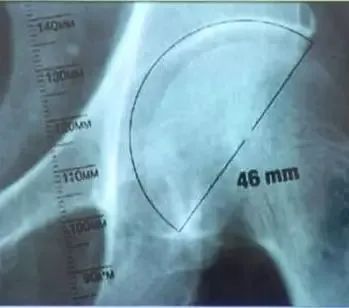

股骨模板测量:

①选择骨盆正位片与合适比例模板;

②股骨距应与模板上的股骨距部相吻合;

③对应颈长的中心应与股骨头中心相吻合;

④经过假体中心的横线应与大粗隆顶点相切;

⑤填充髓腔,注意股骨距的高度。

髋臼模板测量:

②将模板按照45°倾斜角度放入髋臼;

③估计锉后髋臼的大小,内壁的厚度;

④假体的大小应与软骨下最少的截骨量一致;

⑤假体的中心与原髋臼的旋转中心尽可能一致。